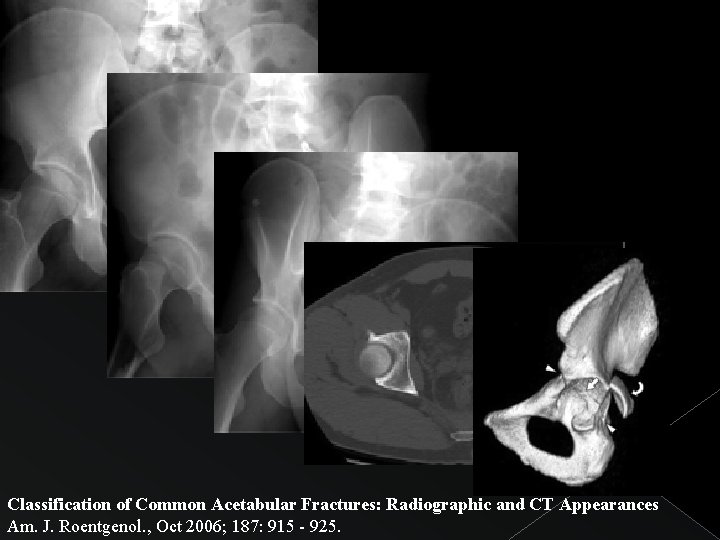

Caso 2

Disrupción del anillo obturador + SIN extensión a pala iliaca FRACTURA en “T”